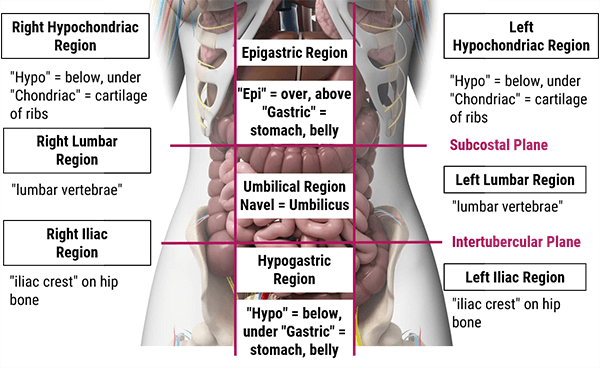

In this section we will explain how the abdominopelvic cavity is divided into 4 quadrants or 9 regions.

The abdominal cavity can be divided into nine different regions using 4 planes, where every organ doesn’t necessarily occupy only one. This division helps with the diagnosis, based on the place where the patient is experiencing abdominal pain.

The nine regions are smaller than the four abdominopelvic quadrants and include: the right hypochondriac, right lumbar, right illiac, epigastric, umbilical, hypogastric (or pubic), left hypochondriac, left lumbar, and left illiac divisions.

- In the Right Hypochondriac region, you will find organs such as the liver, gallbladder, right kidney, and portions of the small and large intestine

- The epigastric region contains portions of the liver, as well as the stomach, pancreas, duodenum, spleen, and adrenal glands

- Whereas the left hypochondriac region contains the spleen, large/small intestines, left kidney, pancreas, stomach, and tip of the liver

- In the right lumbar region, you will mainly find portions of the ascending colon, small intestine, and right kidney

- In the umbilical region, you’ll find the duodenum, the small intestine, as well as the transverse colon

- Whereas in the left lumbar region, you’ll find parts of the descending colon, small intestine, and left kidney

- The right iliac region contains the appendix, cecum, ascending colon, and small intestine

- The hypogastric region contains the bladder, portions of the sigmoid colon, small intestine, and reproductive organs

- And finally, the left iliac region where you will find parts of the sigmoid colon, descending colon and small intestine